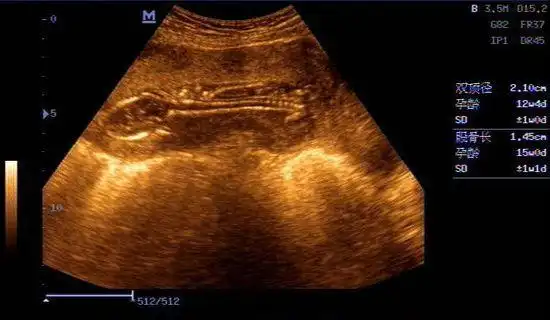

14周男宝b超下的样子,很真实,怀孕的宝妈看过来!

15周大的胎儿b超影像